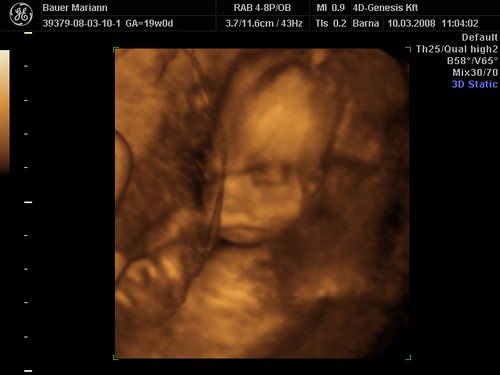

lányok tegnap bevettem egy maltofer vasat és olyan hasmenésem volt most reggel hogy hajjaj ez normális :?: na meg két pici tűszúrásnyi piros pötty lett a pocakomon,jujj megyek mert 10re oda kelll érni a genesisbe látjuk a kicsiket :D jajjj de jó

KépetKépetKépet

Drága picikéim nem voltak túl szereplős hangulatukba úgy kellett kikönyörögni őket a méhlepényből,és még igy sem letek túl élesek a képek.jázmin 266gr ,amy 300gr,jázmin egyszer úgy fejberúgta amyt úgy sajnáltam :D olyan édes formás kiscsajok el vagyok ájulva ,szép egézségesek tele pocakkal,megzabálom őket :D

De nekem eltalálták a 4DGenesisben, nálam tényleg 2 kukis van, igaz, én 2 héttel idősebb terhes voltam, mint te az első 4D-s kukucson.